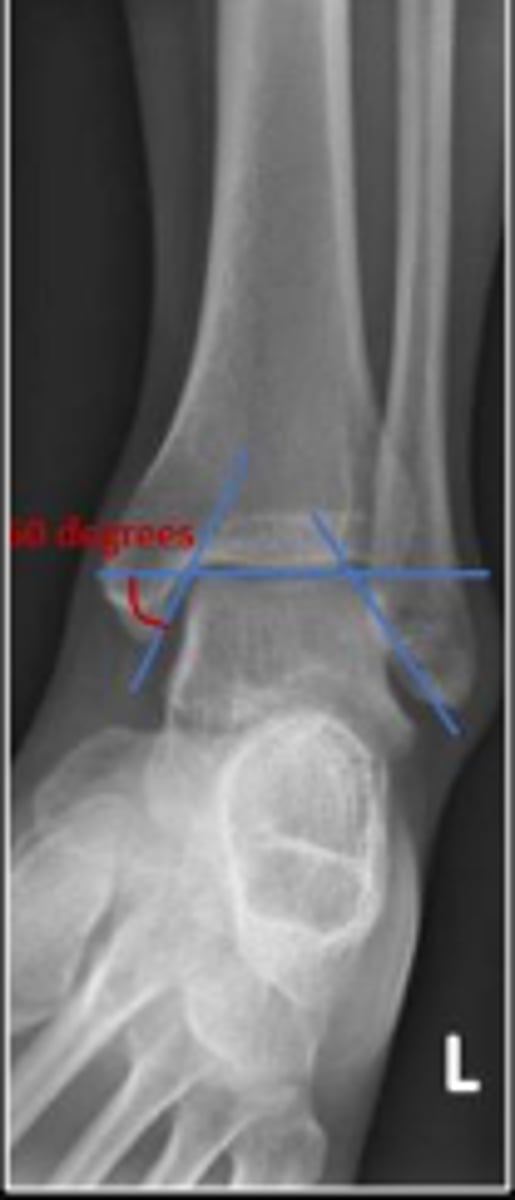

Axial relationship of the ankle

What is the overarching name of the assessment?

Tibial angle & fibular angle

What are the 2 components of the assessment?

Tibial angle

What is the name of the assessment?

Yes

Is the assessment within normal limits?

Fibular angle